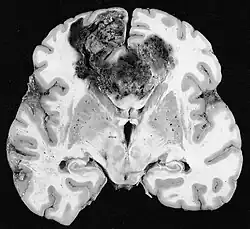

Glioblastoma

Os tumores de células gliais mais comuns e malignos são os glioblastomas. Consistem em uma massa heterogênea de células de astrocitoma pouco diferenciadas principalmente em adultos. Geralmente ocorrem nos hemisférios cerebrais, mais raramente no tronco cerebral ou na medula espinhal. Exceto em casos muito raros, como todos os tumores cerebrais, eles não se estendem além das estruturas do sistema nervoso central.

O glioblastoma pode surgir de uma forma difusa (II. grau) ou um astrocitoma anaplásico (III. grau) se desenvolvem. Neste último caso, é chamado de secundário. No entanto, quando ocorre sem antecedentes ou evidência de malignidade prévia, é referido como primário. Os glioblastomas são tratados com cirurgia, radioterapia e quimioterapia. Eles são difíceis de curar e há poucos casos que sobrevivem além de três anos.

Na ressonância magnética, um tumor intracraniano aparece como uma lesão maciça que pode se tornar mais luminescente após o uso do agente de contraste. No entanto, há sempre uma anomalia de sinal na ressonância magnética, que indica a presença de neoplasia ou edema vasogênico. Normalmente, o aumento da luminescência (realce pelo contraste) é indicativo de um tumor de grau mais alto de malignidade. Um anel contrastante é característico do glioblastoma, com a porção luminescente correspondendo à parte vital do tumor maligno e a área mais escura-hipointense à necrose tecidual.